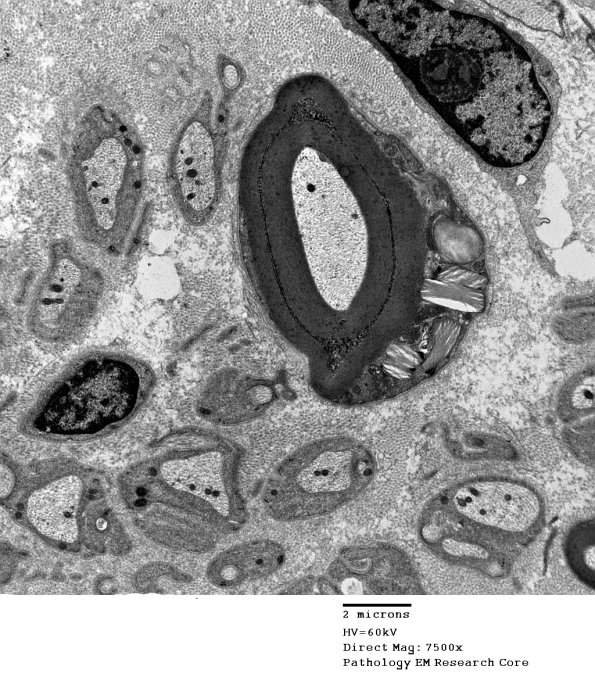

Washington University Experience | PERIPHERAL NEUROPATHY | 3 NORMAL MYELIN & SCHWANN CELLS | 4 Pi Granules (of Reich) | 6A1 Normal nerve, Pi granules (Case 6) EM 2 - Copy

6A1,2 Another case with zebra body-like granules. (Electron micrographs)